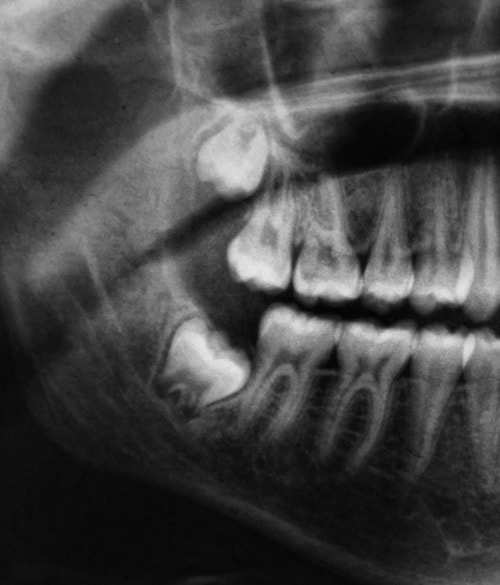

まず虫歯や歯周病の予防の目的として、歯のクリーニング(プラークや歯石の除去)を行います。特に歯石は歯ブラシではとれないので、歯科医師や衛生士が専門の器具を使って取り除くことが必要です。

お子さんにはフッ素塗布も行っています。歯の表面の汚れをとった後にフッ素を塗ることで、汚れが付きにくく虫歯になりにくくなります。特にフッ素は萌出したての永久歯に効果的で、定期的に塗布することをお勧めします。